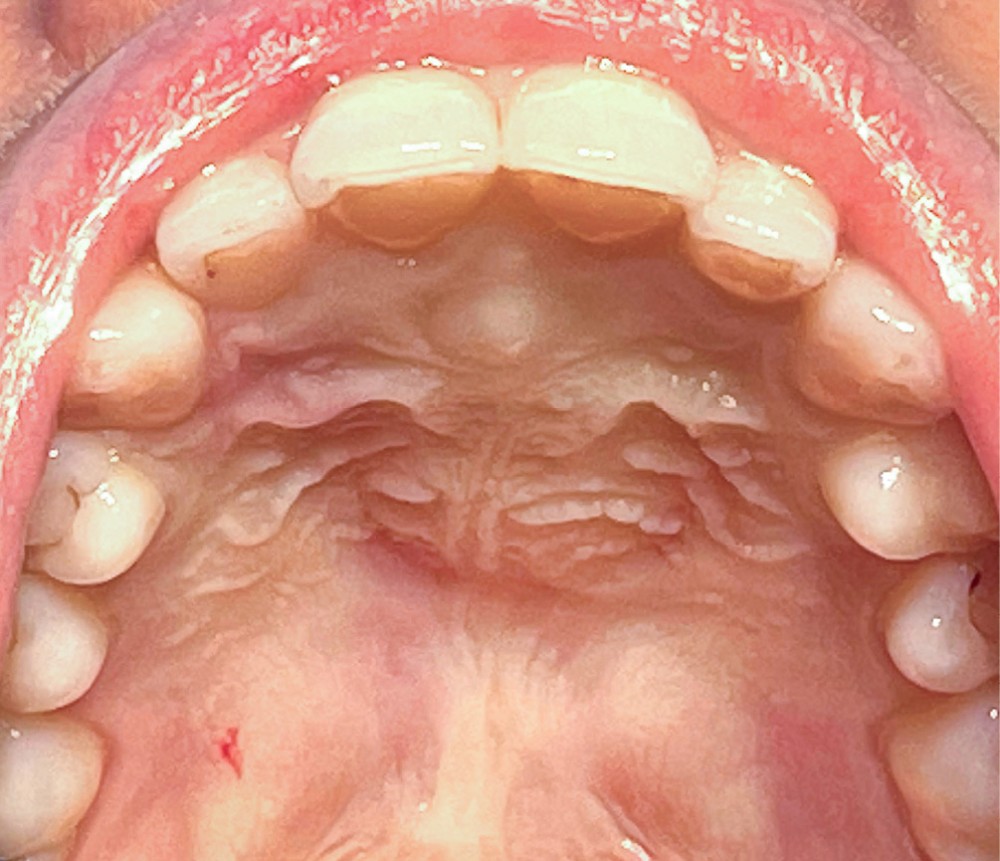

- Les symptômes, lorsqu’ils existent, sont le plus souvent en rapport avec une tuméfaction palatine rétro-incisive (fig. 2) ou des douleurs amenant le patient à consulter.